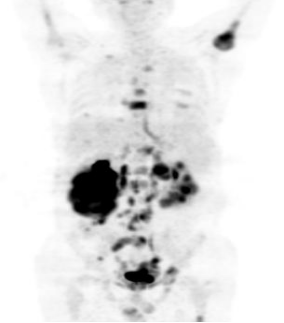

PET-CT能一次進(jìn)行全身斷層顯像,除了發(fā)現(xiàn)原發(fā)部位病變,還可以發(fā)現(xiàn)全身各部位軟組織器官及骨骼有無轉(zhuǎn)移病變,對腫瘤的分期非常有幫助,并提供準(zhǔn)確的穿刺或組織活檢的部位,協(xié)助臨床醫(yī)生制訂最佳的治療方案。幫助放療科醫(yī)生勾畫生物靶區(qū)。例如在肺癌合并肺不張等情況下,放療師很難判斷腫瘤的實(shí)際邊界,PET將有助于確定代謝活躍的病灶范圍,為放射治療(尤其是精準(zhǔn)放療)提供更合理、準(zhǔn)確的定位,降低治療的副作用。

PET-CT可以對腫瘤各種治療的療效進(jìn)行評估并進(jìn)行預(yù)后判斷,指導(dǎo)進(jìn)一步的治療。還可以對治療后腫瘤殘留或復(fù)發(fā)進(jìn)行早期診斷,并與治療后纖維化、壞死進(jìn)行鑒別,同時根據(jù)治療后病灶分布情況進(jìn)行再分期,CT及MRI等結(jié)構(gòu)信息為主的影像手段很難做到這一點(diǎn)。